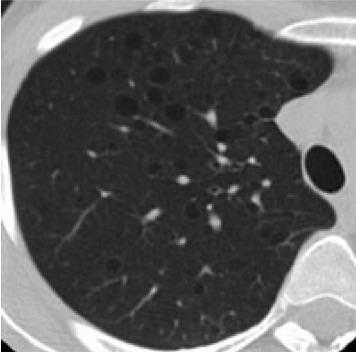

Лимфангиолейомиоматоз легких. Легкие вовлекаются в патологический процесс после 30 лет. Первые клинические симптомы - дыхательная недостаточность и рецидивирующий пневмоторакс.

Фрагмент КТ: множественные кистозные изменения - лимфангиомиоматоз легких

Поражение легких отмечается у пациентов, имеющих туберозный склероз, после 30 лет. На рентгенограмме определяется характерная для множественных легочных кист картина «сотового легкого». Поражение ЖКТ включает опухоли полости рта, дефекты зубной эмали, множественные или одиночные гамартомы в печени, не склонные к малигнизации полипы прямой кишки. Поражение почек сопровождают туберозный склероз в 50-85%. Могут отмечаться ангиомиолипомы, кисты, гломерулосклероз, нефрокальциноз, интерстициальный нефрит, гломерулонефрит. Патология почек выступает второй после поражения ЦНС причиной летального исхода при ТС.

Легочные изменения: исследования выявили кистозные изменения легочной ткани у 40% женщин с ТС.